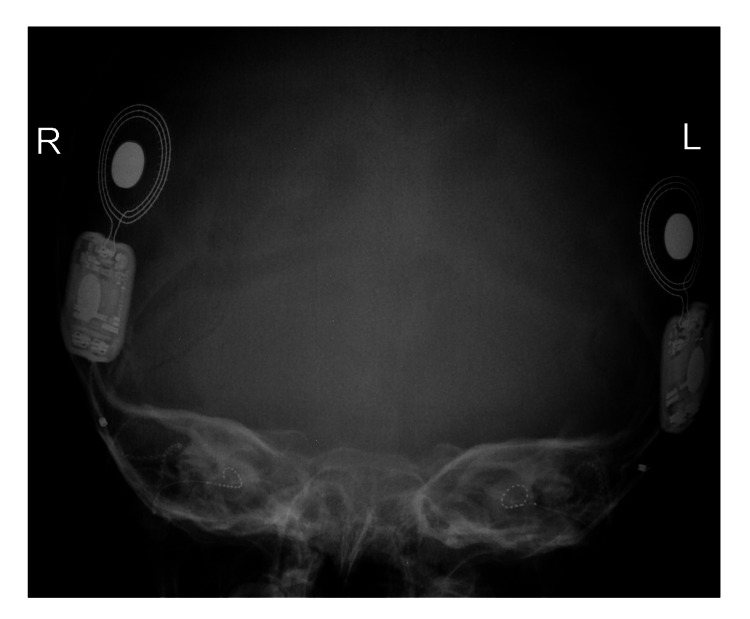

患者被 CI 委員會確定為雙側(cè)植入的候選者。 在三歲零五個月大時,進(jìn)行了雙側(cè)同時人工耳蝸植入(HiRes™ Ultra #D 人工耳蝸,右 HiFocus™ SlimJ 電極和左 HiFocus™ Mid-Scala 電極,Advanced Bionics AG,加利福尼亞州,美國)。 術(shù)后 X 線顯示 CI 陣列有效插入耳蝸內(nèi)(圖 2)。 手術(shù)后第二天開機(jī),并給予兩個 Naida CI Q70 聲音處理器(Advanced Bionics AG,加利福尼亞州,美國)。

An external file that holds a picture, illustration, etc.

Object name is cureus-0014-00000021063-i02.jpg

病例 2 的術(shù)后 X 線顳骨顯示雙耳人工耳蝸電極陣列有效插入